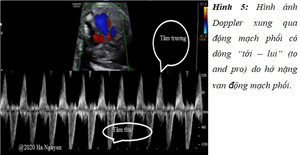

Báo cáo loạt ca: Hội chứng không lá van động mạch phổi